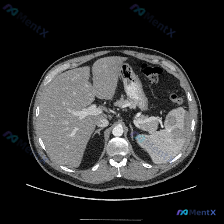

整理了一张很有讨论价值的上腹部平扫CT病例,先把核心信息和我的分析思路放出来: 📋 核心影像表现 图像显示的是上腹部层面,除脾脏外,肝实质、胰腺、胃壁、腹主动脉及腹膜腔在该层面均未见明显异常。唯一的显著异常在脾脏: - 脾脏实质内可见明显的低密度区域 - 边界尚清,但形态欠规则 - 位于脾脏实质内部...

整理了一个近期看到的病例资料和分析思路,分享给大家。 --- 【基本影像信息 - 检查方法: 上腹部CT横断面(软组织窗) - 影像核心表现: - 图像质量良好,解剖结构显示清晰; - 肝脏形态大致正常,肝实质密度尚均匀; - 脾脏:形态饱满,实质内可见较大的类圆形低密度灶,边界尚可辨认,中心密度低...